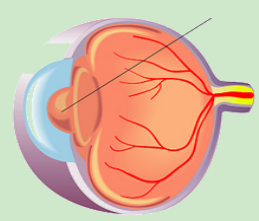

视网膜的小(xiǎo)血管長(cháng)期处于高糖环境中,变得脆弱,就像有(yǒu)裂缝的水管,容易渗漏、出血,从而引起视网膜的病变,可(kě)致视物(wù)模糊、黑影等,甚至失明。

正常视网膜血管